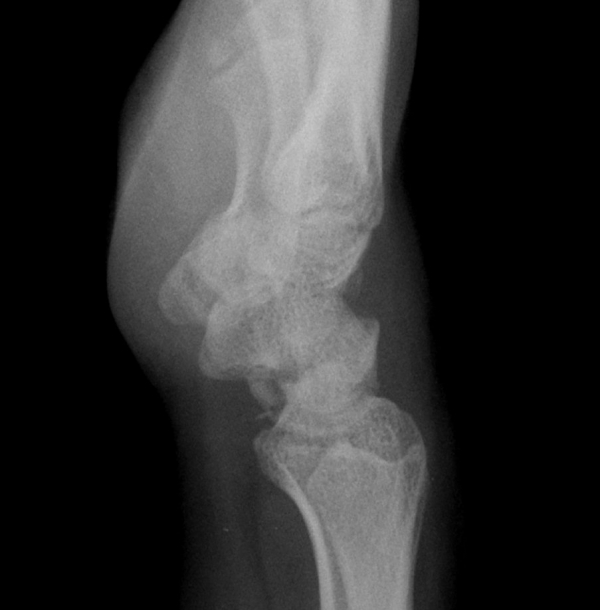

¹æ»ç¼± °Ë»ç : ¼Õ¸ñ Ãø¸é »çÁø¿¡¼­ ¿ù»ó°ñ ÀåÃø¿¡¼­ °ñ±ØÀÌ °üÂûµÊ( »çÁø 4).

ÄÄÇ»ÅÍ ÃÔ¿µ :  ¿ù»ó°ñÀÇ ºÐ¼â°ñÀýÀÌ °üÂûµÊ(»çÁø 5, 6, 7, 8).